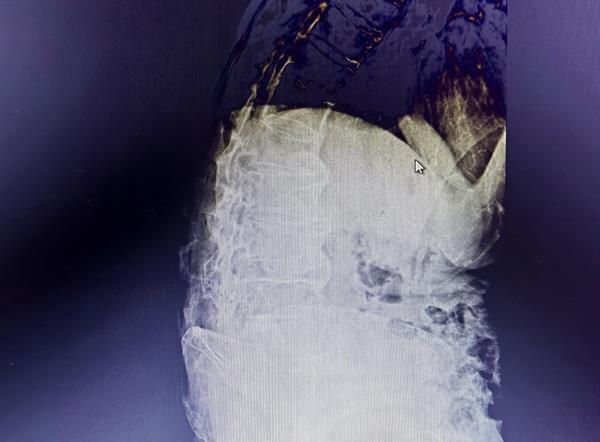

術(shù)前常規(guī)檢查,發(fā)現(xiàn)薛爺爺患有高血壓、慢阻肺等基礎(chǔ)疾病,且有嚴(yán)重的脊柱后突(俗稱(chēng)駝背)。但薛爺爺?shù)母构蓽橡薏∏橐训搅吮仨毷中g(shù)的程度,家屬也十分期待能早日為患者手術(shù)。

患者脊柱CT影像

一般情況下,僅有脊柱后突但患者心肺功能良好,常規(guī)的蛛網(wǎng)膜下腔麻醉因穿刺困難,麻醉風(fēng)險(xiǎn)增高,麻醉醫(yī)師會(huì)改用全身麻醉避開(kāi)前者的弊端;但薛爺爺?shù)臓顩r是二者兼有,實(shí)施全身麻醉的話,由于身體畸形造成的胸腔和腹腔容量減少,呼吸及消化功能損害的風(fēng)險(xiǎn)更大,左右權(quán)衡,細(xì)致考慮,最終確定由麻醉科副主任高峻嶺為薛爺爺實(shí)施穿刺有難度的蛛網(wǎng)膜下腔麻醉。效果理想,薛爺爺成功手術(shù)。